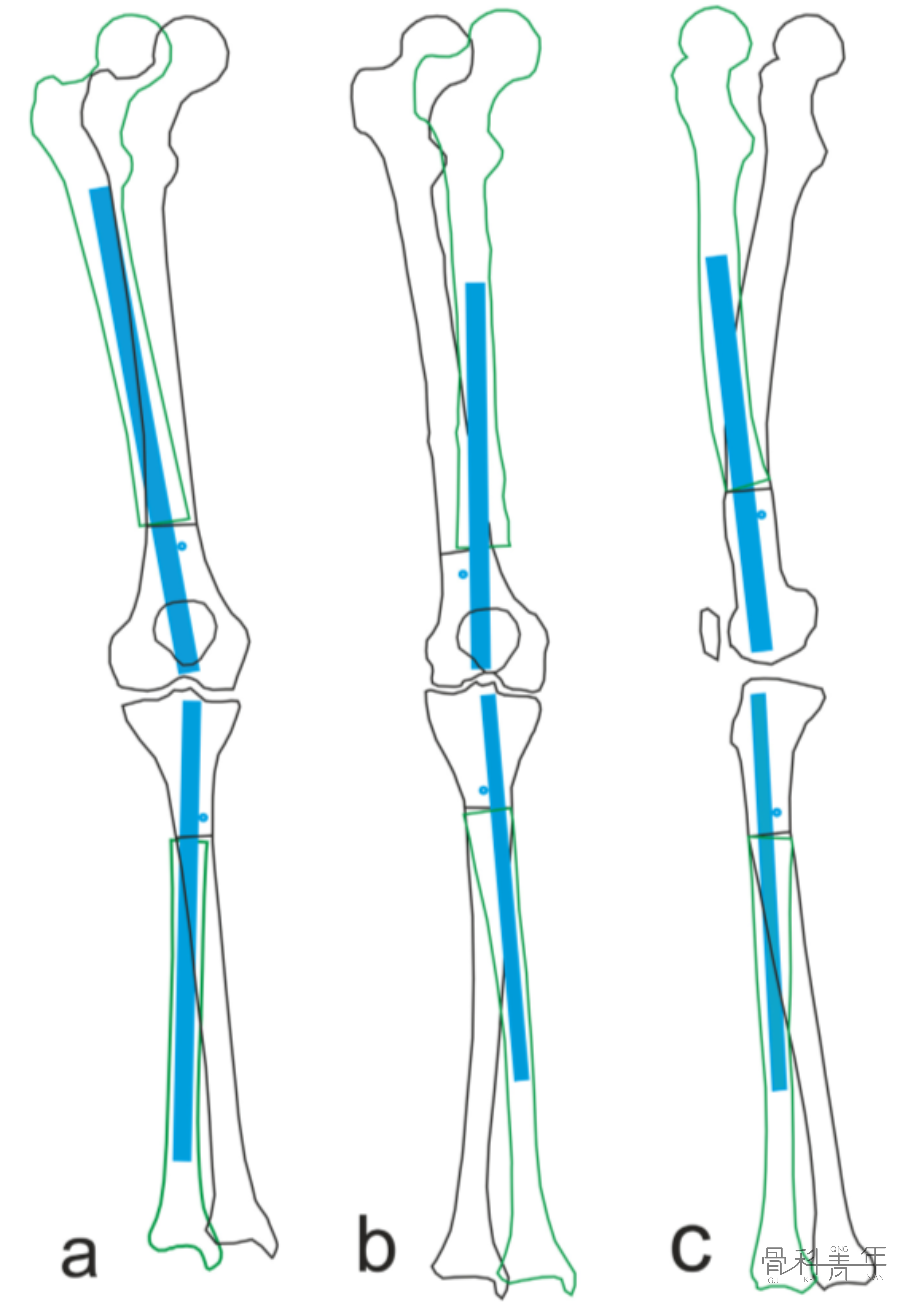

1.沿移位骨块(远干骺端为远端骨块、近干骺端为近端骨块)作一中轴线;

股骨远端骨折示例。沿股骨远端骨块作一中轴线,骨折线与中轴线相交,形成2锐角(Acute angles)。

2.经骨折线作一线与上述轴线相交;

3.相交后形成夹角,辨认出锐角处;

胫骨近端骨折同理。

4.将Poller置于锐角处的干骺端或远端骨块;

将Poller钉置于锐角处。

胫骨近端骨折,同理将Poller钉置于锐角处。

依上述理论及病例解析,不难发现,无论对于股骨或胫骨,无论畸形方向,均可以通过阻挡钉来位置髓内钉位置。各部位及各畸形状况下阻挡钉置入位置如下图: